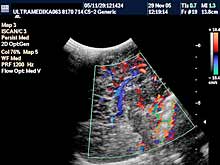

B) Ultrazvučni pregled abdomena-trbuha

Ovaj pregled se savetuje da se

radi bez obzira da li postoji klinička potreba ili ne. Inače najčešća

indikacija je povraćanje u mlazu koja obično počinje oko 3 nedelje

života!

Vrsta pregleda:

- 2D i 3D organa stomaka,

- Broad band CD vaskularizacije

organa a po potrebi primenom CPA i CPD i 3D CPA

- UZ sonda od 5-12 MHz.

- Kompjuterski program je obavezan za ove preglede

u dece!